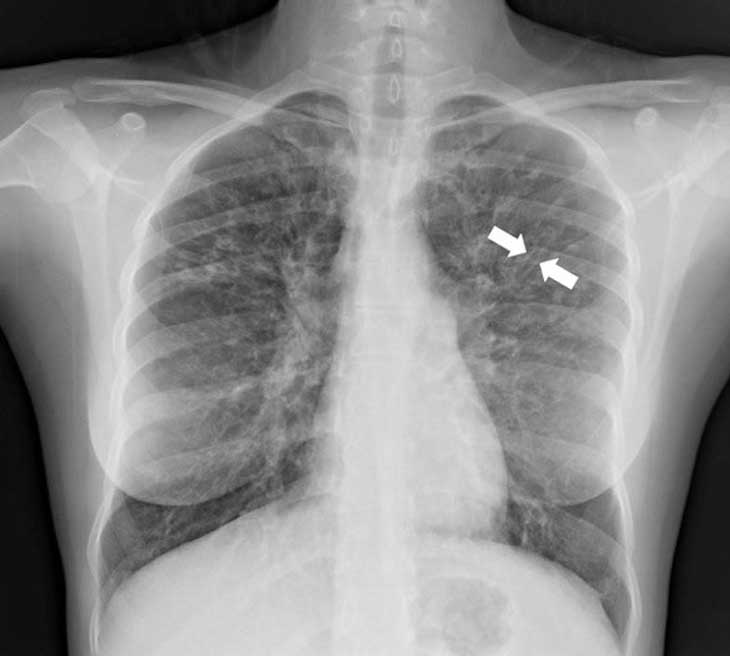

Bệnh giãn phế quản được chẩn đoán bằng hình ảnh X-quang, hầu như luôn đi kèm với chụp CT ở ngực

Chụp CT sẽ thể hiện vùng và mức độ nặng của bệnh giãn phế quản và có thể đưa ra những đầu mối về nguyên nhân của bệnh này. Nhà cung cấp dịch vụ y tế của bạn cũng có thể yêu cầu đo chức năng phổi (các bài kiểm tra về hô hấp) và lấy đờm của bạn để tìm các vi trùng cụ thể. Việc cấy đờm này sẽ giúp xác định kháng sinh nào có hiệu quả tốt nhất trong đợt cấp. Trong một số trường hợp, bác sĩ có thể yêu cầu nội soi phế quản, trong đó một ống dài với đèn và camera ở cuối ống được đặt vào đường thở để lấy chất nhầy ra.